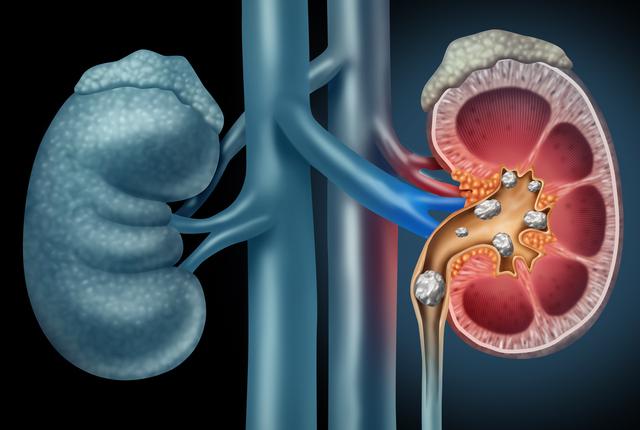

What Are Kidney Stones?

Kidney stones are hard mineral deposits that form in your kidneys when your urine becomes too concentrated with minerals like calcium, oxalate, or uric acid. These stones may remain in the kidney or move down the urinary tract, causing intense pain and complications.